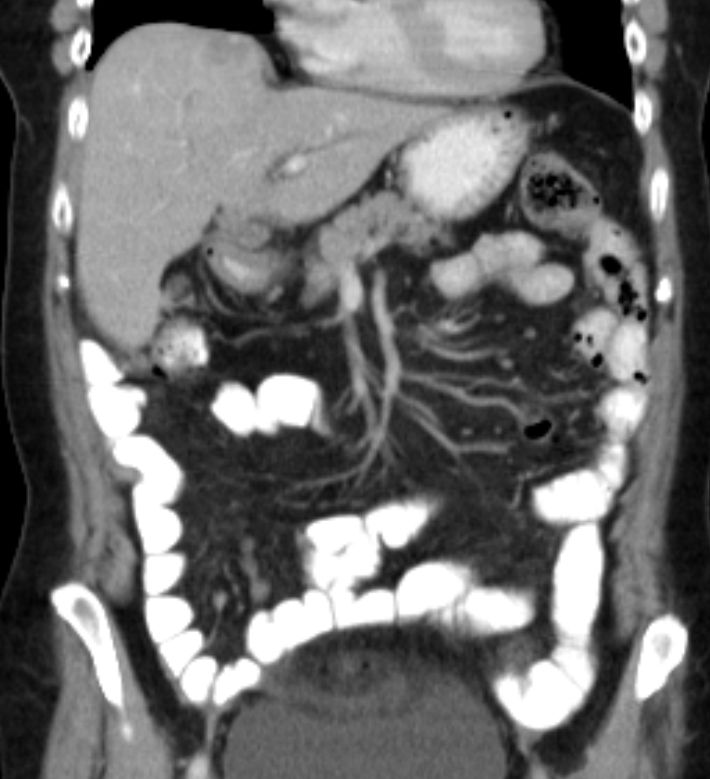

Spätrezidiv 77-jährige Frau bei der vor 13 Jahren ein Ovarialkarzinom behandelt wurde: Hysterektomie, bilaterale Adnexektomie, Omentektomie, Appendektomie, 6 Zyklen Carboplatin/Taxol

Nebendiagnosen: Mammakarzinom links 1977 (Ablatio + Axilladissektion)

Jetzt: peritoneale und Lebermetastasierung, mediastinale Lymphknotenvergrößerung.

Leberpunktion: Adenokarzinom. Die Tumorinfiltrate zeigen angedeutet papillären Strukturmuster. Immunhistologie: CK 7 stark positiv. Nukleär deutlich Östrogen sowie WT1. CK 20, CEA, CDX2, TTF1 negativ.